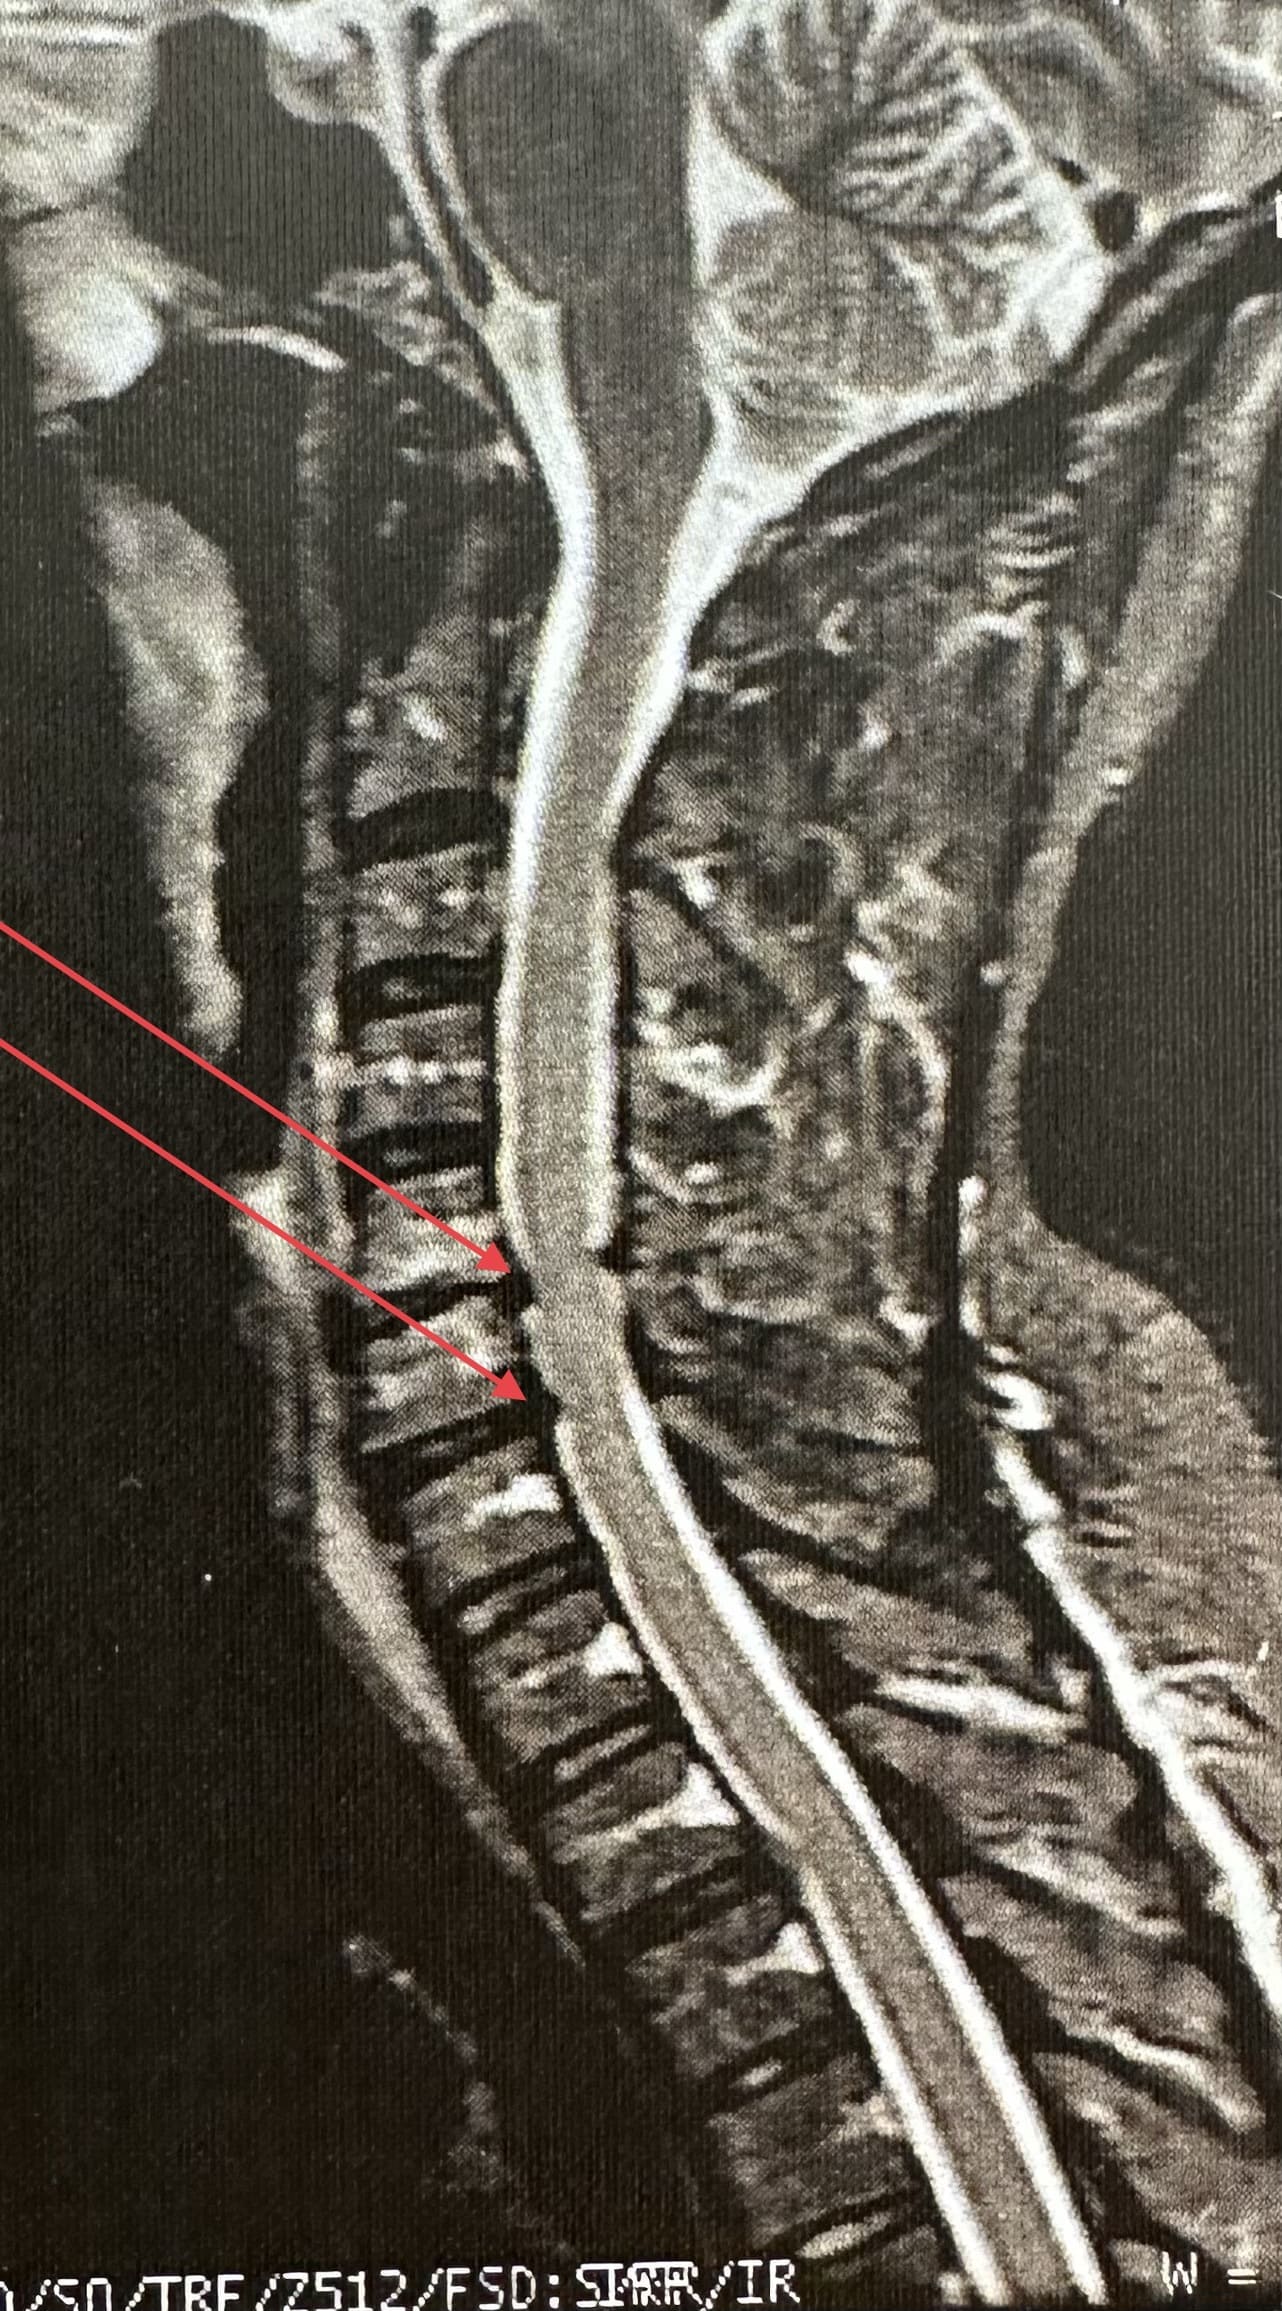

Uma hérnia de disco cervical ocorre quando o material do disco intervertebral se desloca ou se projeta para fora de sua posição normal e comprime as estruturas circundantes, como os nervos ou a medula espinhal.

Exames como ressonância magnética (RM), tomografia computadorizada (TC) e radiografias são frequentemente realizados para diagnosticar a condição da coluna cervical antes de decidir pela cirurgia.